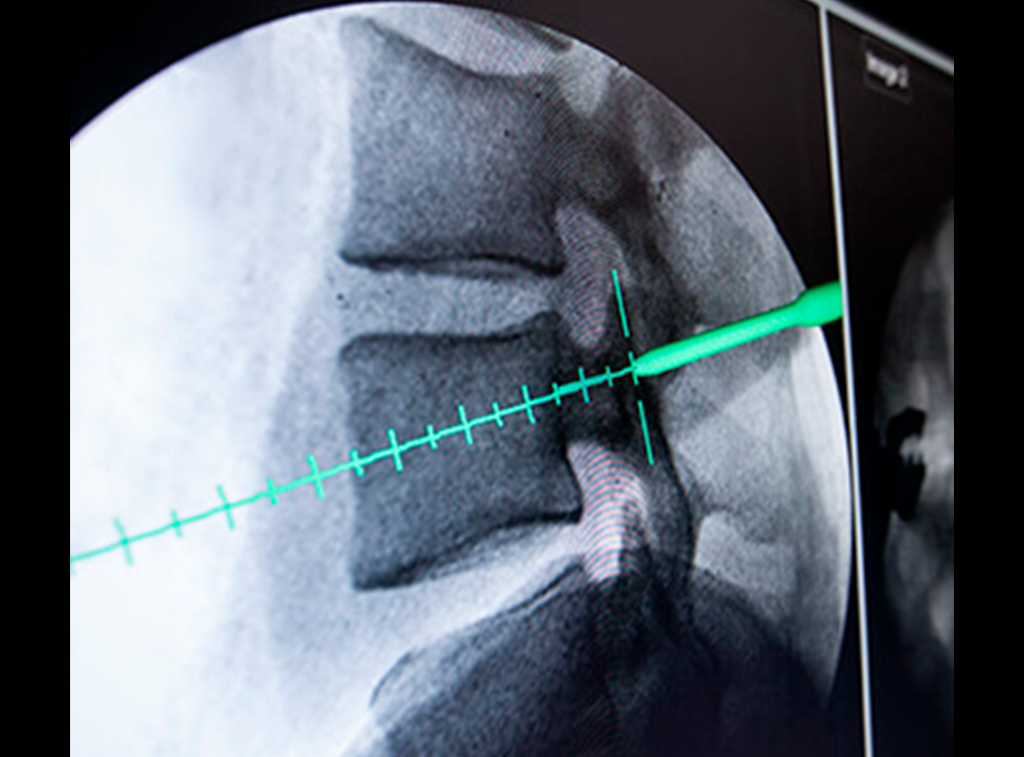

Evaluación médica y estudios

Evaluación médica de cualquier condición de la columna

Fractura de columna

Esto puede suceder después de un accidente u osteoporosis.